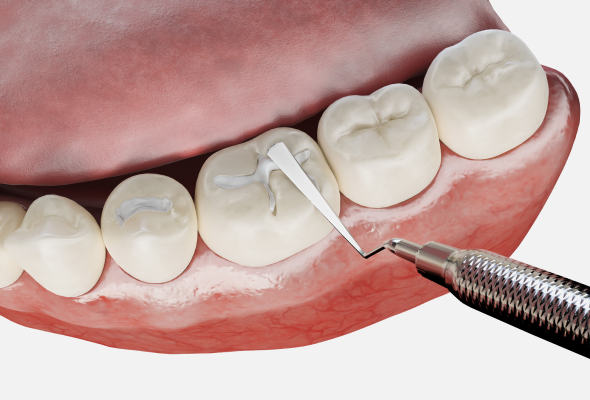

레진치료

충치가 생긴 부위를 제거한 뒤 복합레진 수복 재료를 채워 치아의 형태를 복원하는 치료 방법입니다. 치료 후에는 정상 치아와 유사하도록 매끈하게 마무리하며, 주로 초기 충치 단계에서 적용됩니다.

인레이 치료

충치 부위를 제거한 후 본을 떠 맞춤 제작한 인레이를 접착하는 방식입니다. 레진치료로는 부족한 경우, 비교적 충치 범위가 넓은 경우에 적용됩니다.